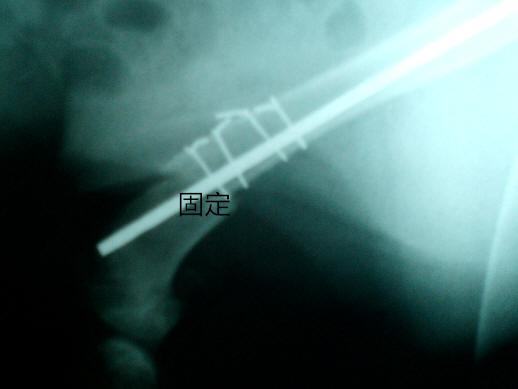

骨折处固定

治疗的话,一般是采用髓内针,不锈钢丝或者接骨板做内固定,配合支架绷带等外固定的辅助治疗方法,恢复效果会更加好。肱骨骨折和其他骨折有不同的地方,它自愈的可能性较高,因此可以不用固定而是采用悬吊或者自由活动的方法,这样子有助于自愈。自愈的快慢和动物的年龄,身体状况,营养状态,受伤程度有关系,幼龄动物,即使骨折端错位,也有恢复的可能,到成年的时候常见不到畸形和跛行。肱骨头骨折,其他的治疗方法没有效果的时候,可以采用肱骨头摘除术,促进形成假的关节,虽然会造成永久性的跛行,但是可以解除疼痛,还可以保持动物的经济价值,可以生产生育。